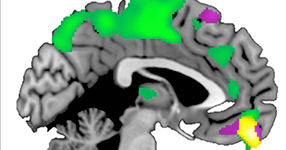

Image: The ventromedial prefrontal cortex (yellow) is larger in those that tend to be more trusting of others compared to those that tend to be less trusting of others.

"Another finding that we observed was for a brain region called the amygdala. The volume of this area of the brain, which codes for emotional saliency, was greater in those that were both most trusting and least trusting of others. If something is emotionally important to us, the amygdala helps us code and remember it."